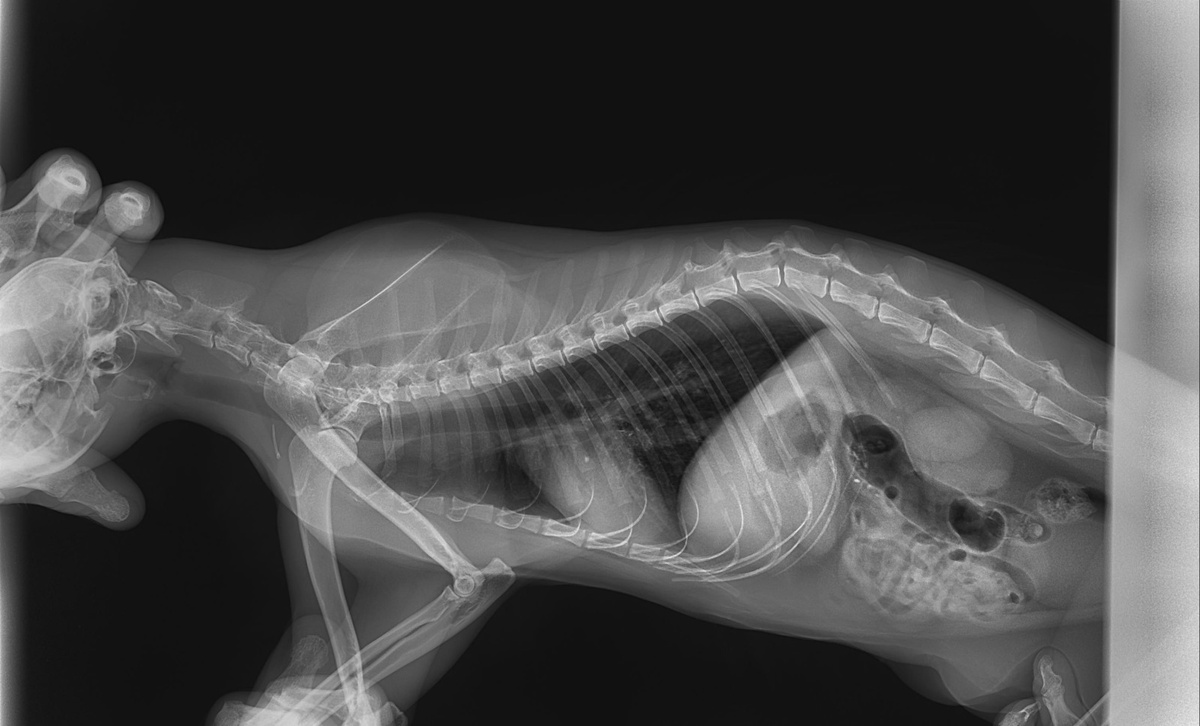

А весь день я переписывалась с разными специалистами. Спасибо всем большое, кто откликнулся. Оказывается, на дзене я нашла настоящих друзей! К вечеру все таки сошлись на том, что у Мурзика инородка.

Снимок, сделанный накануне.

В этой клинике Мурзику делали узи, рентген и взяли кровь. Отпустили нас домой, сказав, что жизни ничего не угрожает. Они на снимке не увидели инородку. Я показала снимок ещё нескольким специалистам и мне сказали - она там есть. Мы просто потеряли целые сутки.

В итоге мы позвонили сразу в третью клинику. Скинули все снимки и нам говорят - видим инородку. Рентген сделать не сможем, сможем сразу вскрыть, посмотреть и вынуть. Мы сразу туда. При ощупывании Мурзика выяснилось, что у него ещё и кишка в кишку зашла, а это плохо. Если не выпрямится, то придётся этот кусок отрезать и сшивать. И как приживется - не известно. В общем, оставили его в клинике.